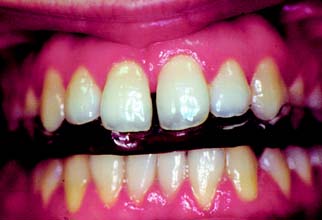

Oral habits consisting of involuntary rhythmic or spasmodic nonfunctional gnashing, grinding, or clenching of teeth, in other than chewing movements of the mandible, that may lead to occlusal trauma is known as bruxism (Fig. 4-18). This activity may be diurnal, nocturnal, or both. Although bruxism is initiated on a subconscious level, nocturnal bruxism is potentially more harmful because the patient is not aware of it while sleeping. Therefore, it can be difficult to detect, but it should be suspected in any patient exhibiting abnormal tooth wear or pain. The prevalence of bruxism is about 10% and is less common with age.18 The etiology of bruxism is often unclear. Some theories relate bruxism to malocclusion, neuromuscular disturbances, responses to emotional distress, or a combination of these factors.19 A study on cohort twins has demonstrated substantial genetic effects20; the condition has been related to sleep disturbance21; and the symptoms of bruxism are three times more common in smokers.22 Altered mastication has been observed in subjects who brux23,24 and may result from an attempt to avoid premature occlusal contacts (occlusal interferences). There may also be a neuromuscular attempt to “rub out” an interfering cusp. The fulcrum effect of rubbing on posterior interferences creates a protrusive or laterotrusive movement that can cause overloading of the anterior teeth, with resultant excessive anterior wear. It is common for wear on anterior teeth to progress from initial faceting on the canines to the central and lateral incisors. Once vertical overlap diminishes as the result of wear, posterior wear facets are commonly observed. However, the chewing patterns of normal subjects can be quite varied, and the relationship, if any, between altered mastication and occlusal dysfunction is not clear.25

Fig. 4-18 Extensive abrasion (tooth wear) resulting from parafunctional grinding.

(Courtesy of Dr. M. Padilla.)